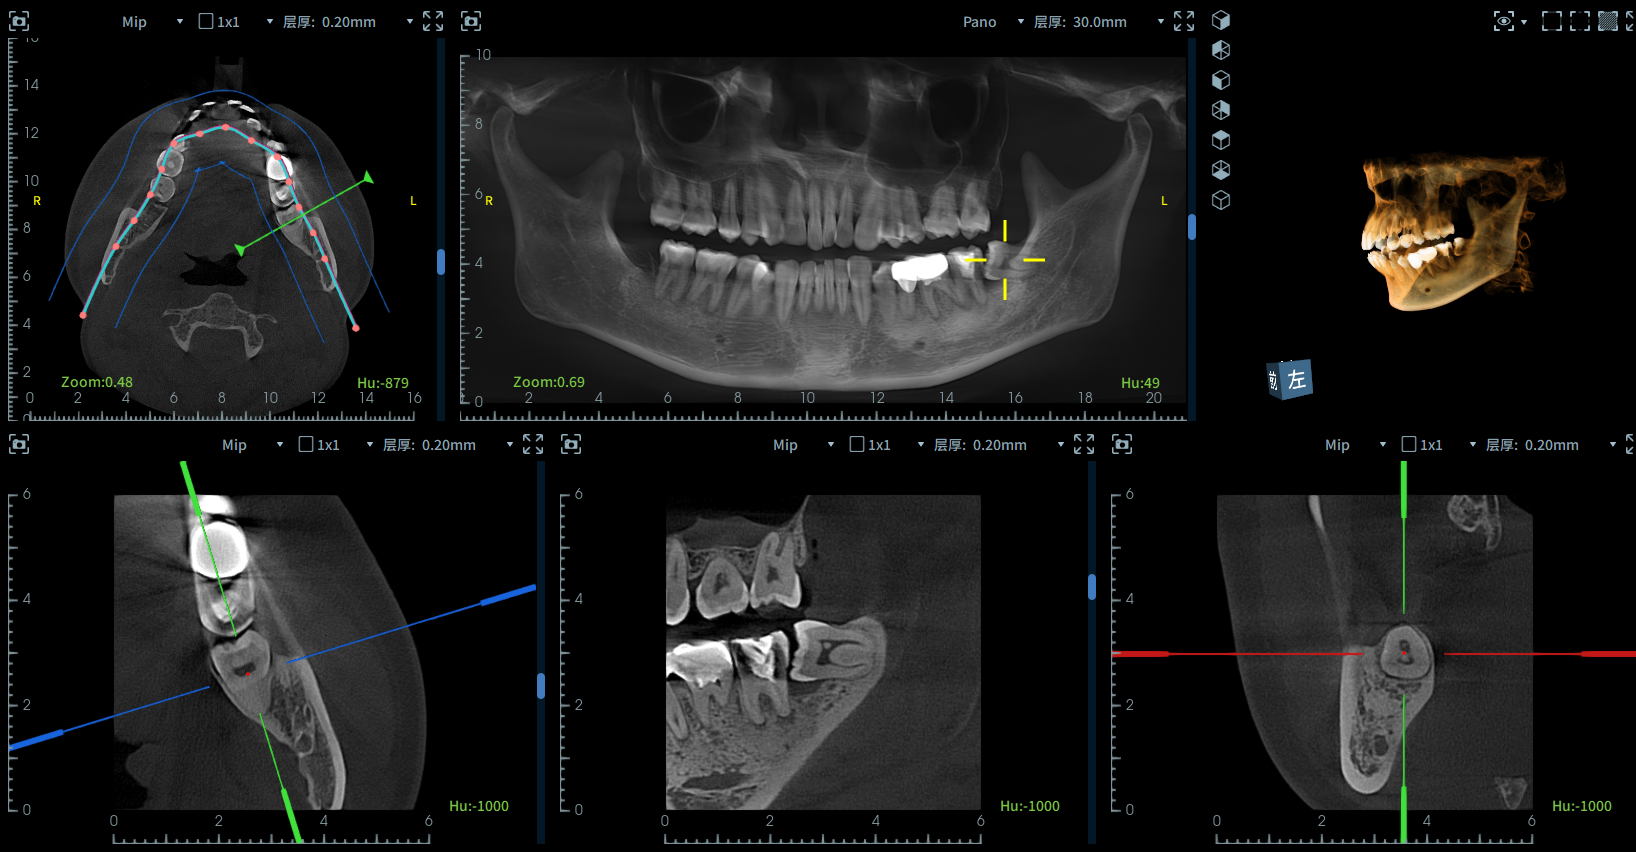

拧不开的瓶盖千万别上嘴[感动] (这颗牙前前后后已经花两千多啦)

完成了根管治疗,今天取神经没打麻药,被队友称赞可以吹一辈子[傻笑]